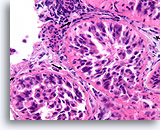

Invasief Ductaal carcinoom, Borst FNA, Celblok.

Met behulp van histologische coupes kunnen in sommige ductale carcinomen invasieve patronen geïdentificeerd worden [4]. Het invasieve patroon bestaat uit ductale cellen die binnen een actieve stroma groeien zonder lobulaire of ductale architectuur. De maligne cellen vertonen geen voorspelbare relatie met stromale referentiepunten en lijken het stroma onder willekeurige hoeken binnen te dringen. De kenmerken van invasiviteit worden in de volgende afbeeldingen geïllustreerd.

40X

Invasief Ductaal carcinoom, Borst FNA, Celblok.

Met behulp van histologische coupes kunnen in sommige ductale carcinomen invasieve patronen geïdentificeerd worden [4]. Het invasieve patroon bestaat uit ductale cellen die binnen een actieve stroma groeien zonder lobulaire of ductale architectuur. De maligne cellen vertonen geen voorspelbare relatie met stromale referentiepunten en lijken het stroma onder willekeurige hoeken binnen te dringen. De kenmerken van invasiviteit worden in de volgende afbeeldingen geïllustreerd.

40X